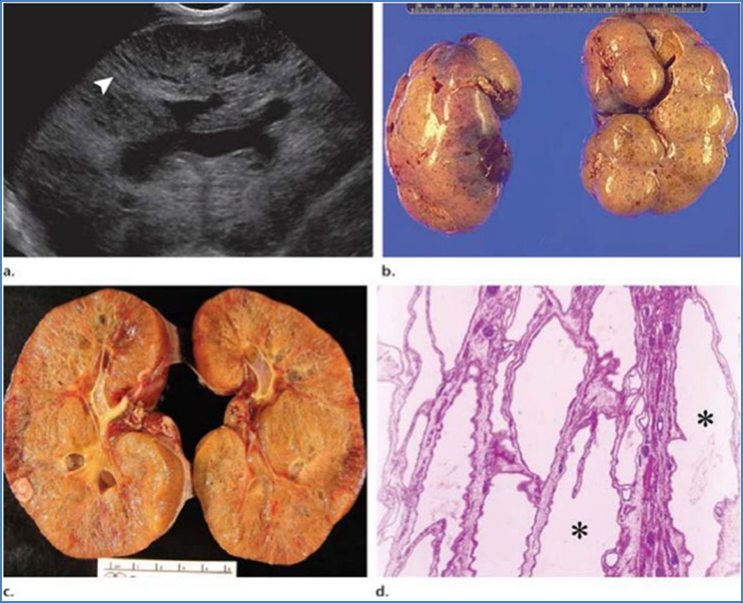

Morphology

- Bilateral enlarged kidneys

- Numerous cysts of varying size

- Some normal renal tissue remains

- Intermittent haemorrhage within cysts possible

- Bilaterally enlarged kidneys with spongy appearance

- Uniform, small cysts